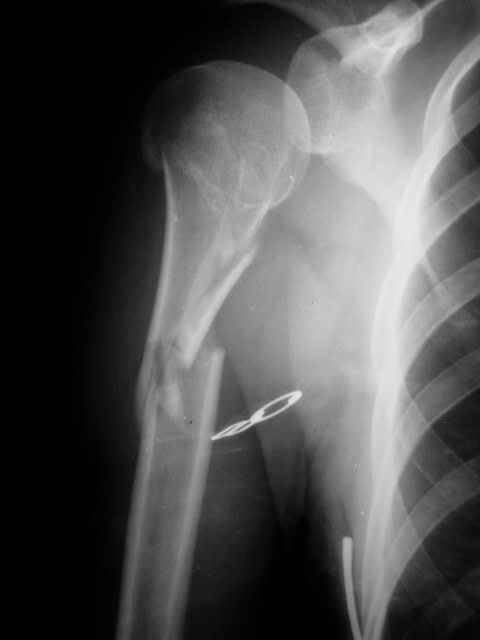

Уважаемые коллеги! Пациентка госпитализирована для оперативного лечения. Интерлокинг плечевой кости в клинике ни разу не производился. Есть сомнения:1)короткий проксимальный фрагмент позволит ли заблокировать плечо надежно? и 2)нужно ли начинать применять интерлокинг с двойного оскольчатого метадиафизарного перелома, а не остановиться на аппарате внешней фиксации? За сообщениями в форуме слежу давно, но реального общения с коллегами, работающими интерлокинг много и красиво маловато. А вопросов ух как много. Спасибо Александру Челнокову за курацию данной темы.

Уважаемый Алексей. Остановитесь на классической гипсовой повязке. В прямой проекции вы уже вылечили - надо ли оперировать вообще. Если так же стоит в боковой - то зачем. Плечо срастается неплохо, а без нашей агрессии и того лучше. Если стоит нехорошо в другой плоскости - то метод выбора остеосинтеза - тот чем Вы владеете хорошо. Новое - на более простых пациентах. С ув. А Рыков. Хабаровка.

Случай хрестоматийный длч проведения БИОС. Современные конструкции имеют большее количество винтов в проксимальном отделе, особенно этим отличается Stryker - T2, в АО - кроме винтов еще используется запирающийся извитой клинок, кроме того можно установить стержень с помощью компрессирующего устройства, что значительно улучшит стабильность. Послеоперационное ведение - на ваше усмотрение в зависимости от оценки первичной стабильности,

можно сразу начинать активные движения, при сомнениях вести более осторожно. Операция быстрая, бескровная при наличии ЭОПа и инструментов.

В этом отделе переломы срастаются обычно без проблем, в небольшие сроки, ось хорошая, по крайней мере в прямой проекции, если в боковой также - зачем операция?